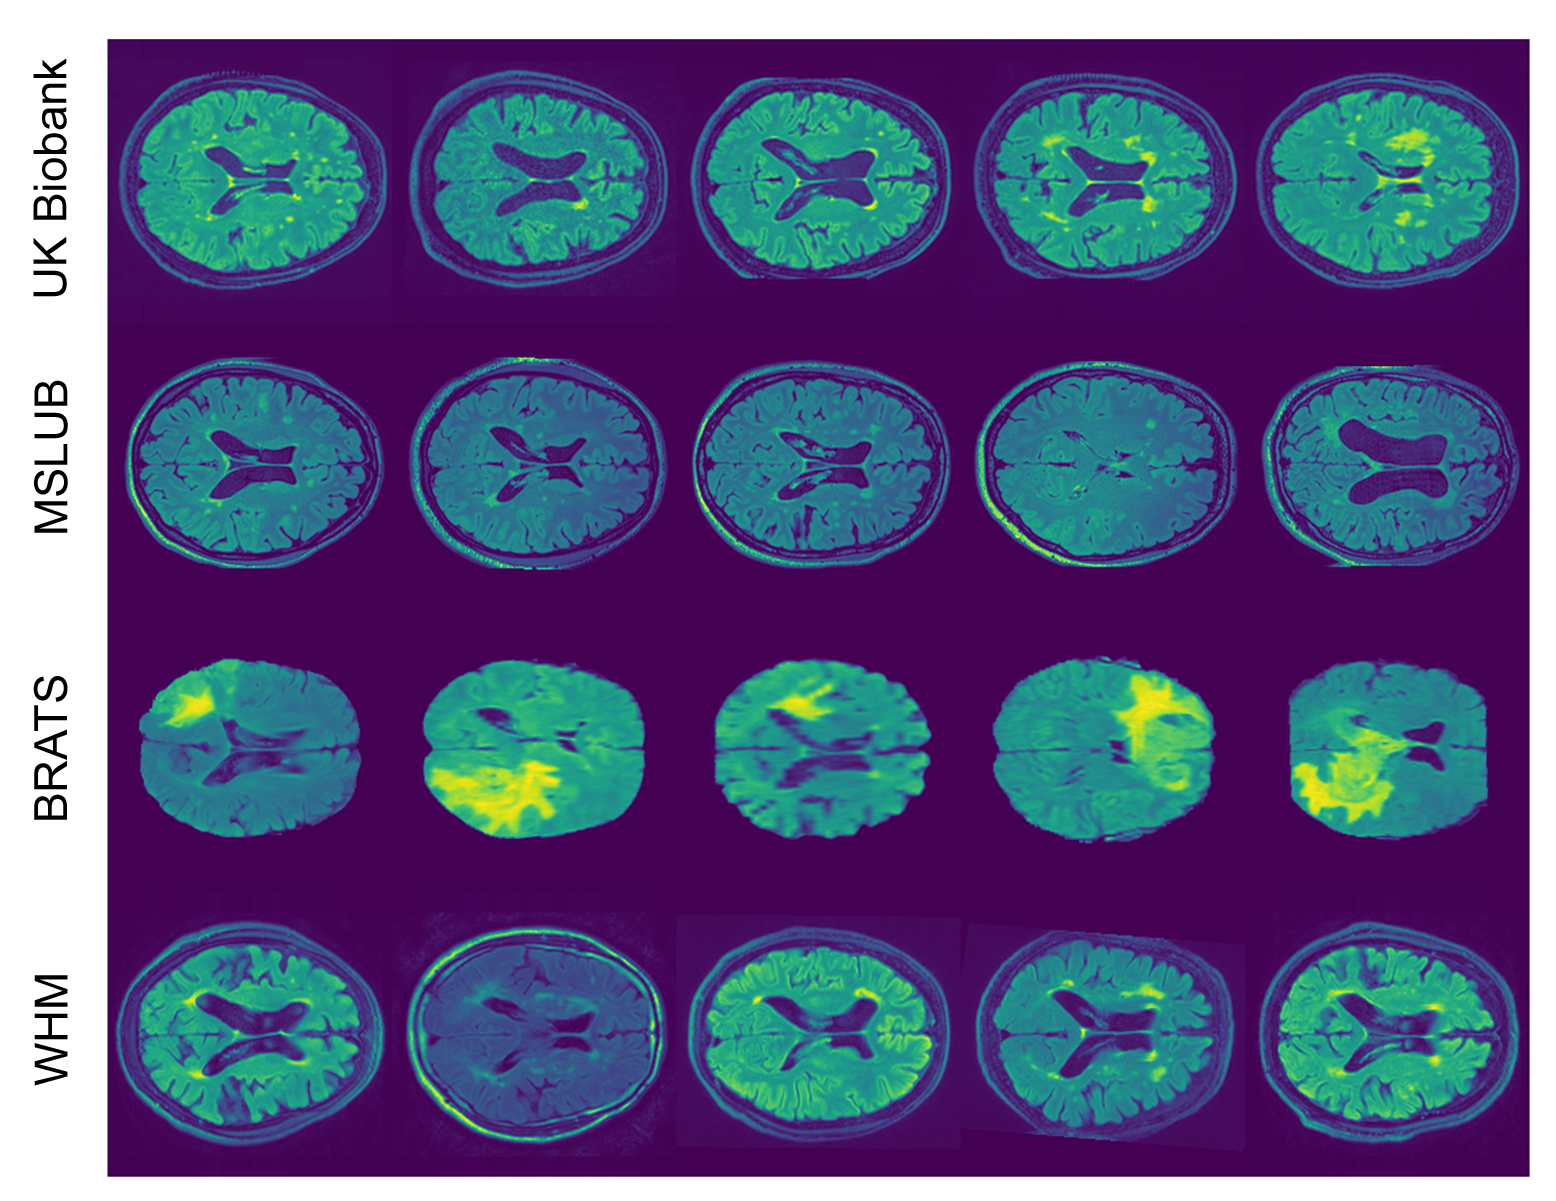

4.3 Experiment #3 – Anomaly Segmentation on Real Neuroimaging Data

To evaluate our method’s performance on real world lesion data, we used the FLAIR images from the UK Biobank (UKB) dataset Sudlow et al. (2015). We selected the 15,000 subjects, and their respective FLAIR images, with the lowest white matter hyperintensities volume, as provided by UKB, to train our models, as these subjects were the most radiologically normal. Then, we used 18,318 subjects from the remaining UKB dataset to evaluate our method to detect white matter hyperintensities (WMH).

In order to test for model generalisability, we also evaluated our method on three other datasets that also had FLAIR imaging data: the Multiple Sclerosis dataset from the University Hospital of Ljubljana (MSLUB) dataset Lesjak et al. (2018), which contains multiple sclerosis lesions; the White Matter Hyperintensities Segmentation Challenge (WMH) dataset Kuijf et al. (2019); and the Multimodal Brain Tumor Image Segmentation Benchmark (BRATS) dataset Bakas et al. (2017, 2018); Menze et al. (2014) that contain tumours (more information about the datasets and pre-processing on appendix A).

In our experiment, we used three datasets: the UK Biobank (UKB) dataset Sudlow et al. (2015), the White Matter Hyperintensities Segmentation Challenge (WMH) dataset Kuijf et al. (2019), the Multimodal Brain Tumor Image Segmentation Benchmark (BRATS) dataset Bakas et al. (2017, 2018); Menze et al. (2014), and the Multiple Sclerosis dataset from the University Hospital of Ljubljana (MSLUB) dataset Lesjak et al. (2018) (Figure LABEL:fig:S5).

fig:S5

The UKB is a study that aims to follow the health and well-being of 500,000 volunteer participants across the United Kingdom. From these participants, a subsample was chosen to collect multimodal imaging, including structural neuroimaging. Here, we used an early release of the project’s data comprising of 33,318 HC participants. More details about the dataset and imaging acquisition can be found elsewhere Alfaro-Almagro et al. (2018); Elliott and Peakman (2008); Miller et al. (2016). The UK Biobank dataset has available a mask for hyperintensities white matter lesions obtained using BIANCA Griffanti et al. (2016); Jenkinson et al. (2012). We selected the 15k subjects with the lowest lesion volume to train our VQ-VAE model.

The BRATS challenge is an initiative that aims to evaluate methods for the segmentation of brain tumours by providing a 3D MRI dataset with ground truth tumour segmentation annotated by expert board-certified neuroradiologists Bakas et al. (2017, 2018); Menze et al. (2014). Our study used the 2018 version of the dataset composed by the MR scans of 420 patients with glioblastoma or lower grade glioma. The images were acquired with different clinical protocols and various scanners from multiple (n=19) institutions. Note, the available images from the BRATS dataset were already skull stripped.

The WHM dataset is an initiative to directly compare automated WMH segmentation techniques Kuijf et al. (2019). The dataset was acquired from five different scanners from three different vendors in three different hospitals in the Netherlands and Singapore. It is composed by 60 subjects where the WMH were manually segmented according to the STandards for ReportIng Vascular changes on nEuroimaging (STRIVE) Wardlaw et al. (2013). The MSLUB dataset is a publicly available dataset for validation of lesion segmentation methods. The dataset consists of 30 images from multiple sclerosis patients that were acquired using conventional MR imaging sequences. For each case, a reference lesion segmentation was created by three independent raters and merged into a consensus. This way, we have access to a precise and reliable target to evaluate segmentation methods. Full description regarding data acquisition and imaging protocol can be found at Lesjak et al. (2018).

In our study, we used the FLAIR images from these three datasets to evaluate our models. For each of these FLAIR images, the UKB and WMH datasets had a white matter hyperintensity segmentation map, the BRATS dataset had a tumour segmentation map, and the MSLUB dataset had a white-matter lesion segmentation map. We also used T1w and brain mask to perform the MRI pre-processing.